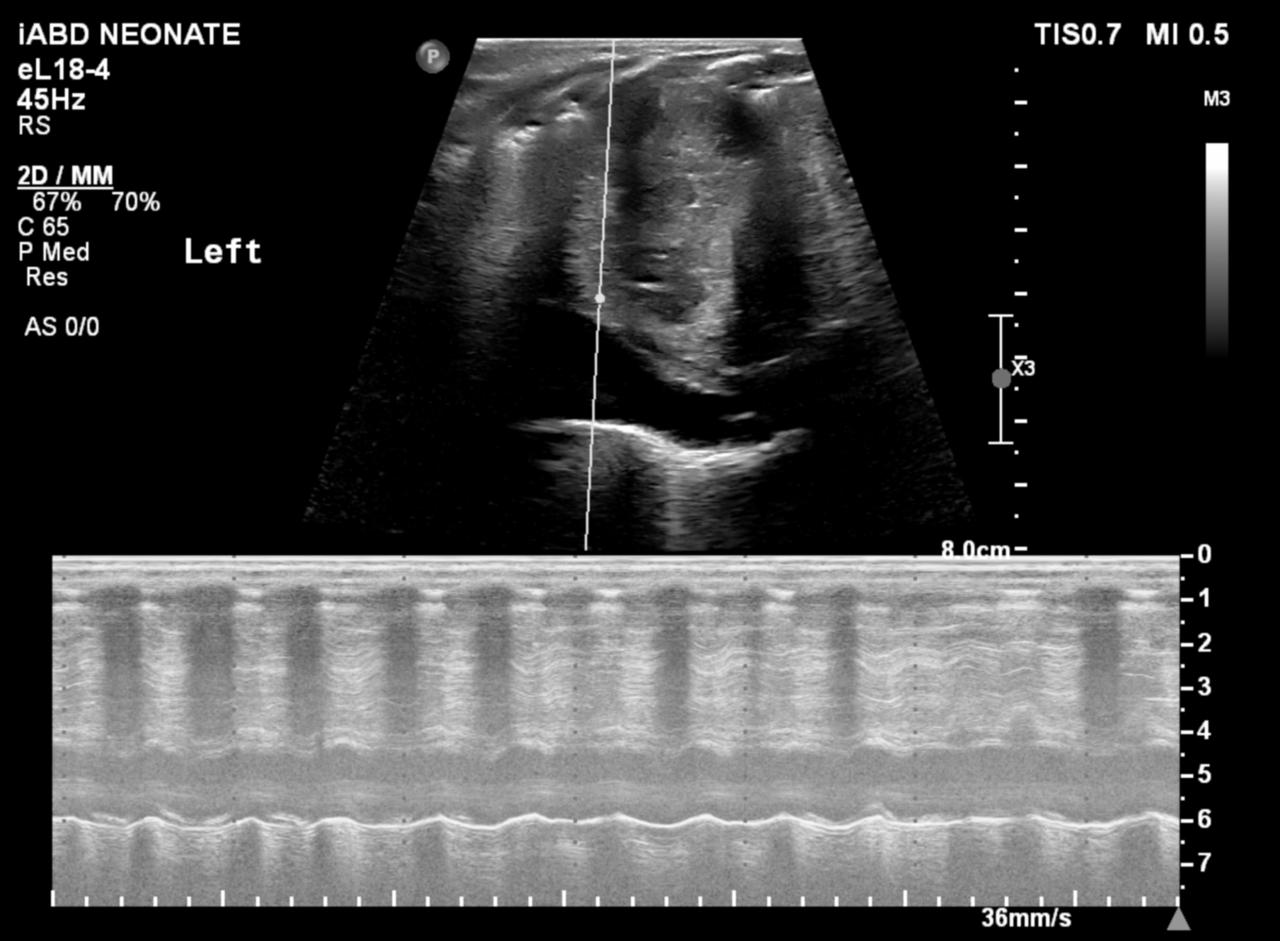

Figura 2: Ultrasonografie la 1 luna post operator la un pacient cu transpoziție de mari vase operată în perioada neonatală: evaluare în modul M – amplitudine sever redusă a mișcărilor diafragmului stâng.

Ecografia este un bun înlocuitor pentru fluoroscopia și poate fi efectuată la pat cu pacientul întins, dacă poate respira în această poziție. Este mai ușor să evaluezi copiii cu ultrasunete cu evitarea riscul de iradiere. Ecografia în timp real este efectuată în plan axial pentru a compara cele două hemidiafragme simultan. Modul M suplimentar coronal sau sagital poate ajuta la cuantificarea gradului de mișcare a fiecărui hemidiafragm individual. Criteriile de diagnostic la copii includ mișcarea paradoxală, excursia mai mică de 4 mm și o diferență >50% între excursia unui hemidiafragm față de celălalt.